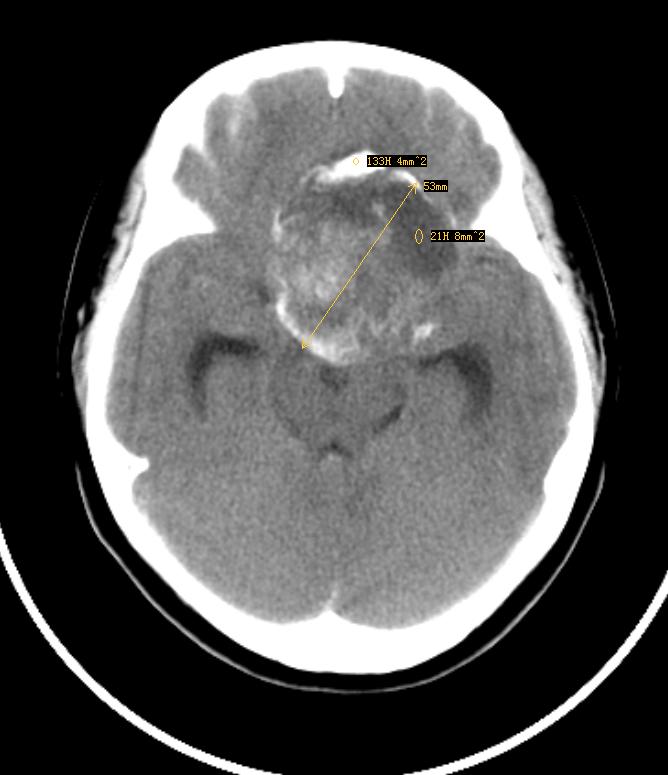

鞍上见一巨大椭圆形、分叶状高、等、低混杂密度肿块,明显占位效应,侧脑室额角、三脑室及四脑室内见高密度区,脑室系统扩大。

定位:鞍上池,肿块呈囊实性,并可见蛋壳样和斑块样钙化,患者13岁,有视力障碍。考虑颅咽管瘤!

鞍上占位,肿块为囊实性,并可见蛋壳样和斑块样钙化。第三、四脑室及侧脑室前角积血,符合颅咽管瘤伴发出血。

鞍上囊实性肿瘤,瘤较大,部分生长于第三、四脑室,并向后推压中脑。其囊壁可见“壳”样钙化,实质部分有不规则斑片状钙化及出血。与周围组织有粘连。因所提供影像不全,故蝶鞍形态不明确,但蝶骨大翼骨质有破坏。

意见:颅咽管瘤,伴出血(出血源于肿瘤脑室部分,顺脑脊液弥散)。

分析:1、鞍上肿瘤表现为囊实性者应首先考虑颅咽管瘤,其余肿瘤,如脑膜瘤、生殖细胞瘤等表现为囊实性是相当罕见的。2、实质部分密度较高,对于颅咽管瘤来说,尚应考虑有钙质沉着和肿瘤内存在较多角蛋白的因素。但因三、四脑室内有高密度影,因而诊断肿瘤伴出血。